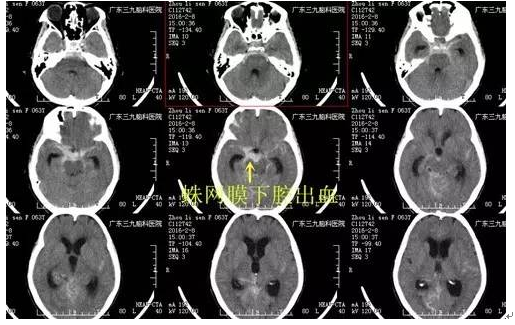

周阿姨,63岁,突发性头痛20小时,就诊当地医院CT示:蛛网膜下腔出血。为求进一步治疗,来我院就诊。入院后完善相关检查,检查提示:右侧后交通动脉瘤,左侧颈内动脉动脉瘤,行介入栓塞治疗去除动脉瘤。病人经系统治疗后颅内血肿完全吸收,头痛缓解,康复出院。